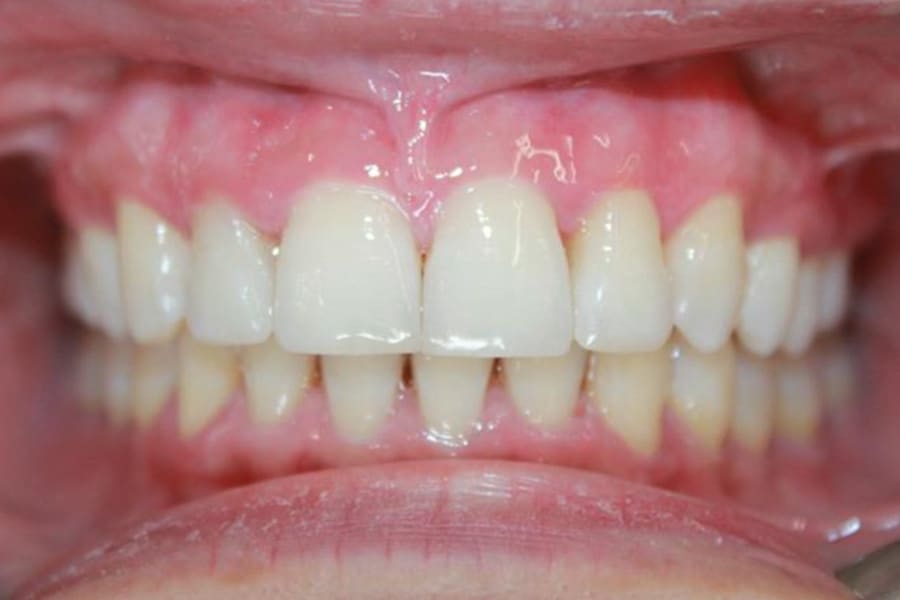

A 35-year-old woman presented with concerns of crowding, bruxism, and bite misalignment, which were associated with a class II malocclusion that would require a combination treatment of expansion, distalization, and molar derotation. ClearCorrect® aligner therapy (Straumann, clearcorrect.com) was selected as the primary modality, as the patient requested a non-invasive, esthetic treatment. The treatment plan was designed to be completed within 6 months of active aligner therapy. Class II elastics were prescribed, and the ClearCorrect FLEX case plan was chosen to allow for refinements, as needed. After comprehensive digital records were taken, the first set of aligners was delivered, engagers were bonded, and the patient was instructed to wear aligners on a 14-day cycle with full-time class II elastic wear. To enhance efficiency, more engagers were placed, including posterior attachments, to maximize control over molar distalization and anchorage. Interproximal reduction of 0.3 mm was performed in a few contacts at the initial appointment to facilitate space closure and alignment. Due to the complexity of the correction and the patient’s history of bruxism, a lower 3-3 bonded retainer was placed, and retainers were fabricated for both arches. The patient expressed a high level of satisfaction with the ClearCorrect aligner therapy, noting the comfort and esthetics of the aligners and the ability to achieve a fully corrected class II occlusion in just 6 months of treatment.

ClearCorrect’s advanced material properties, digital planning tools, and precise movement control allow for comprehensive class II correction in an accelerated timeframe with minimal auxiliaries and excellent patient compliance.